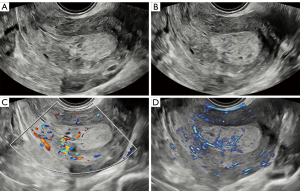

Figures 4,5 show the typical ultrasonic images of a nonmalignant endometrium. Figure 4 depicts the ultrasonic images of endometrial hyperplasia. The vascularity in the endometrium was scored higher on MVFI (score =2) than on CDI (score =1). Figure 5 provides ultrasonic images of endometrial polyps. The vascularity in MVFI was more abundant (score =4) than that in CDI (score =3).

Abundant vascularity was observed in endometrial malignancy, as depicted in Figures 6,7. Specifically, Figure 6 shows the high vascularity in focal atypical hyperplasia. The subjective score was higher for MVFI (score =4) than for CDI (score =2). A similar outcome can be observed in Figure 7, which shows endometrioid adenocarcinoma. CDI showed moderate vascularity (score =3), while MVFI showed abundant vascularity (score =4). MVFI exhibited more abundant vascularity in both nonmalignant and malignant endometria as compared with CDI.